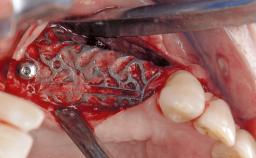

Reconstructive Treatment of a Peri-Implantitis Defect at an Implant in a Mandibular Molar Site

In this case, Mario Roccuzzo utilizes surgical bone regeneration treatment around implant 46 using a bone graft substitute and a connective tissue graft to resolve peri-implant inflammation, reduce the probing depths, and prevent further progression of disease.

A 58-year-old-male patient was referred in February 2007 for implant placement in the right mandibular molar area. Two tissue level implants were inserted at sites 44 and 46, respectively, to support a three-unit fixed dental prosthesis (FDP).